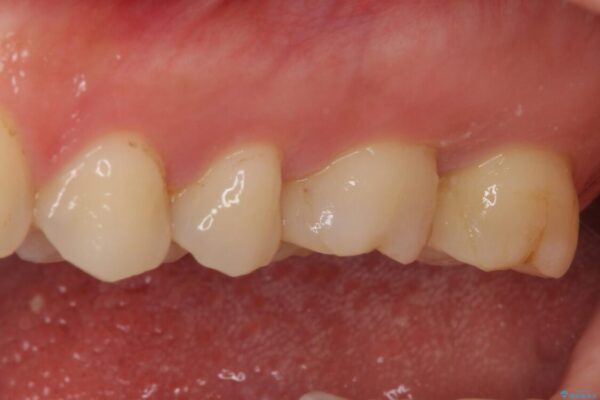

初診時は神経組織の生活反応が認められましたが、2日後に処置を行ったときには、既に反応はなくなっている状態でした。

神経組織は壊死が始まっておりましたが、初回処置後には痛みを感じることもなくなり、2回目に無事に根管治療を終えることができました。

治療後

• 奥歯がズキズキと痛む 奥歯の虫歯治療 治療後画像